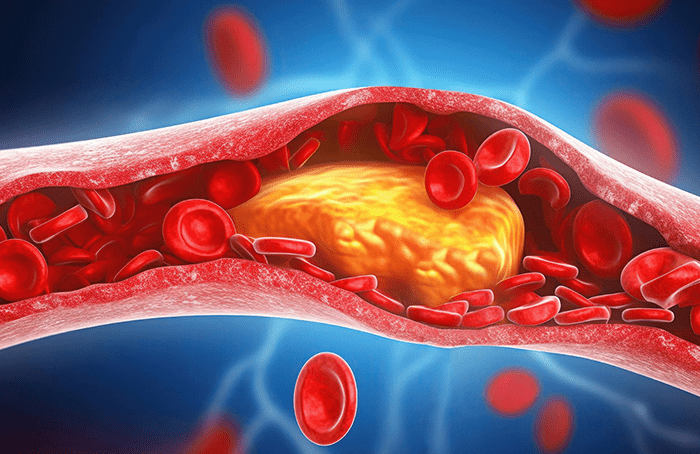

Control de colesterol y triglicéridos

Estrategias terapéuticas para normalizar los niveles de colesterol y triglicéridos en sangre y reducir el riesgo de infartos cardiacos, cerebrales, embolias, etc.